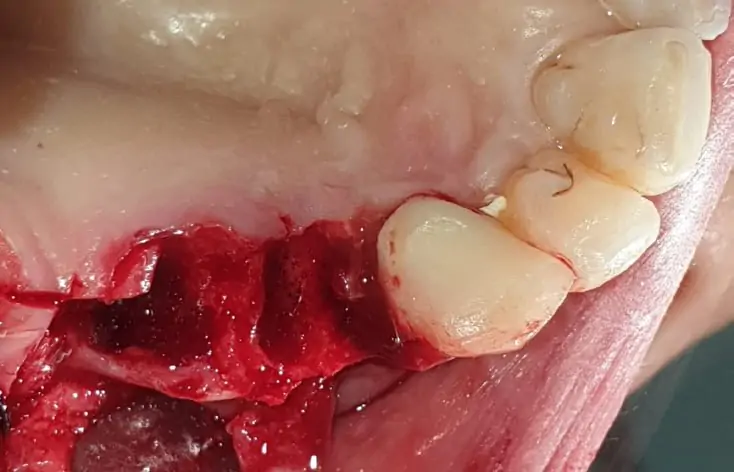

From the first radiographic examination (OPT and CT scan) there is an evident periapical granuloma and pain with pressure on 14 and 15, while 17 element is parodontopathic, moreover there is a lack of bone in 16 and 17 area with chronic infections at the level of the maxillary sinus. Due to the clinical history of the patient it was not advisable to go for a sinus lift, it has been planned the insertion of a pterygo implant and 2 post extractive EV implants. During the surgery, biomaterial (Novocor from B&B Dental) was added to the insertion of the implants  to remodel the ridge horizontally, given the evident bone deiescence. Two temporary provisional titanium abutments were then inserted, welded with a two titanium bar. We inserted 2 EV implants to reach a better primary stability. As the patient is bruxist the crowns have been totally unloaded. The pterygoid implant will be loaded on a second session.